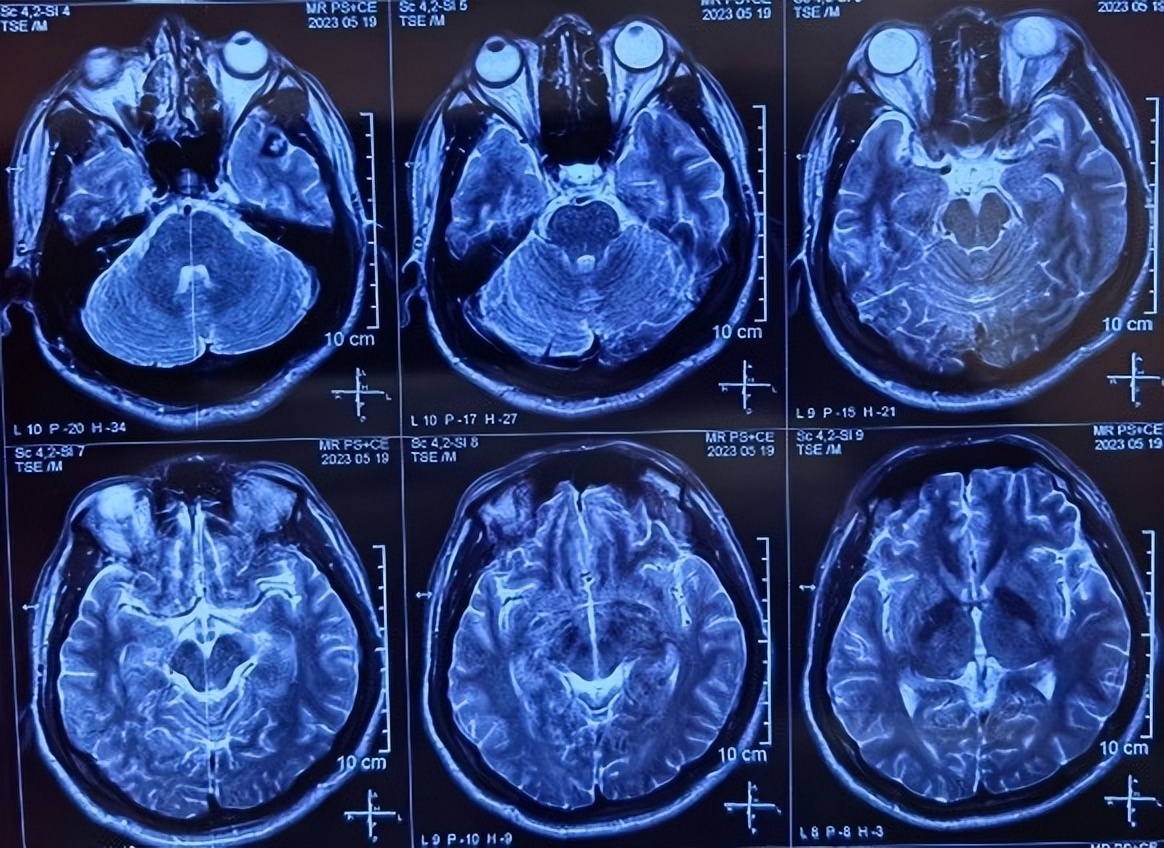

头MRI: 位于左颞极的海绵状血管瘤